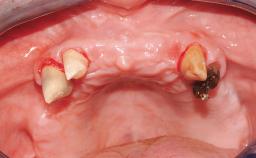

Immediate Loading of Six Implants in the Mandible and Six Implants in the Maxilla and Final Restoration with Full-Arch CAD/CAM Metal Framework FDPs Involving Digital Planning and Guided Surgery

Immediate loading of dental implants is increasingly popular with clinicians and patients. The idea of delivering a restoration directly after implant insertion,combined with a less invasive procedure (flapless protocol), has made treatment protocols involving dental implants more accessible to dentists and patients. However,immediate-loading concepts require sophisticated and exact planning. To facilitate this, conventional panoramic tomographs and periapical radiographs are often taken with the patient wearing a radiographic template simulating the preoperative prosthetic design. However, these radiographs do not provide all the necessary information. In addition, some protocols call for conventional surgical templates fabricated on the diagnostic cast. These will inform the bone drilling points and drill angles, but do not reference the underlying anatomical structures or provide exact 3-D guidance.